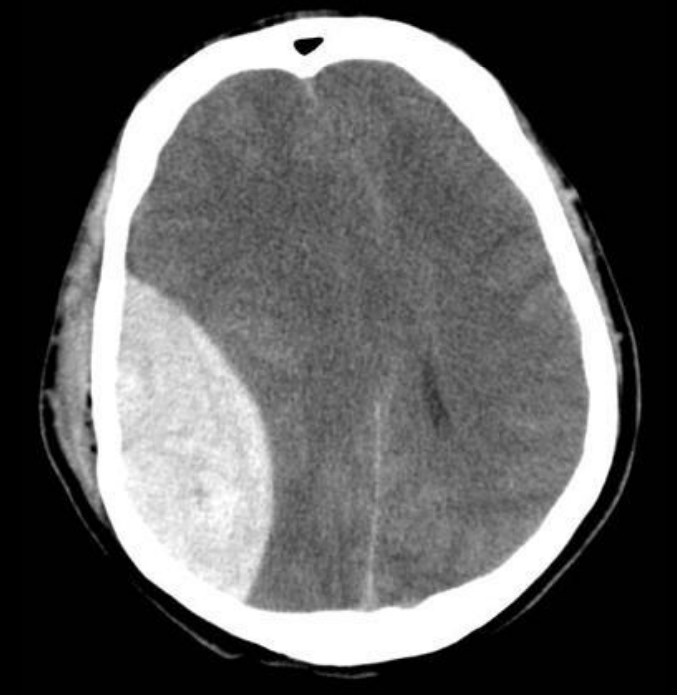

Hematoma epidural en TC

Colección biconvexa/lenticular, NO cruza suturas

arterial

11

Arteria afectada en el hematoma epidural

A. Meníngea media

12

Epidural: hallazgo asociado casi siempre

• Fractura

• Herniación/efecto masa